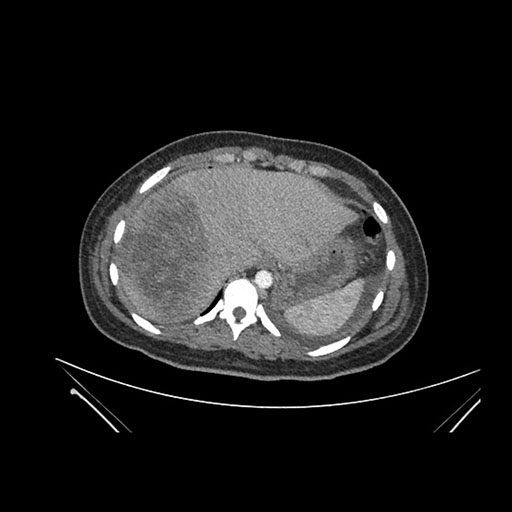

Imaging Analysis

Look through the patient's CT scan to identify any areas of concern for the necessary procedure.

Axial Venous

Based on initial findings, which issue(s) would you be most concerned about?